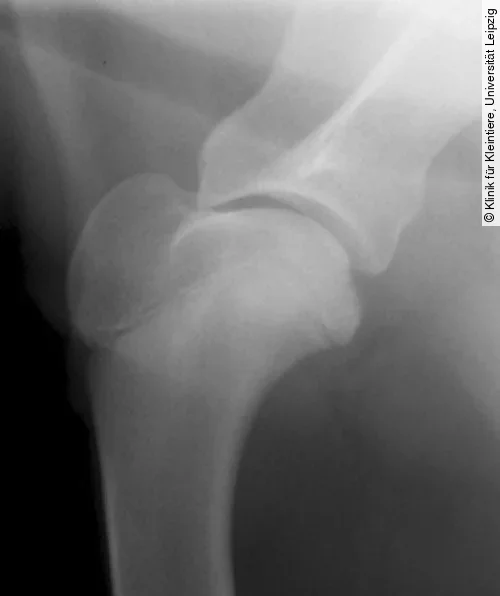

Projektionsradiografie Kniegelenk

Für die Darstellung der OCD am lateralen und medialen Condylus femoris wird eine mediolaterale und eine kraniokaudale oder kaudokraniale Röntgenaufnahme benötigt. Obwohl die mediolaterale Aufnahme häufig schon pathognomonische Anzeichen der OCD zeigt, ist eine kraniokaudale oder kaudokraniale Projektion erforderlich, um festzustellen, welcher Kondylus betroffen ist [4].

Die Röntgenbilder können Veränderungen wie eine Abflachung der Gelenkoberfläche an einem der beiden Femurkondylen (meist Medialfläche lateraler Kondylus), einen konkaven Defekt am subchondralen Knochen (mit oder ohne angrenzende Sklerose) oder selten mineralisierte Knorpelschuppen zeigen (Abb. [ 6 ], Abb. [ 7 ]).

Differenzialdiagnostisch kann es zu einer Verwechslung der normalen Fossa extensoria (Ursprung M. extensor digitorum longus) mit einer OCD-Läsion kommen. Die Fossa resultiert aber im Gegensatz zur OCD-Läsion nicht in einem Defekt der Gelenkfläche (kraniokaudale Projektion) und ist auf der mediolateralen Aufnahme deutlich weiter kranial und proximal lokalisiert (Abb. [ 6 ]) [4], [22].